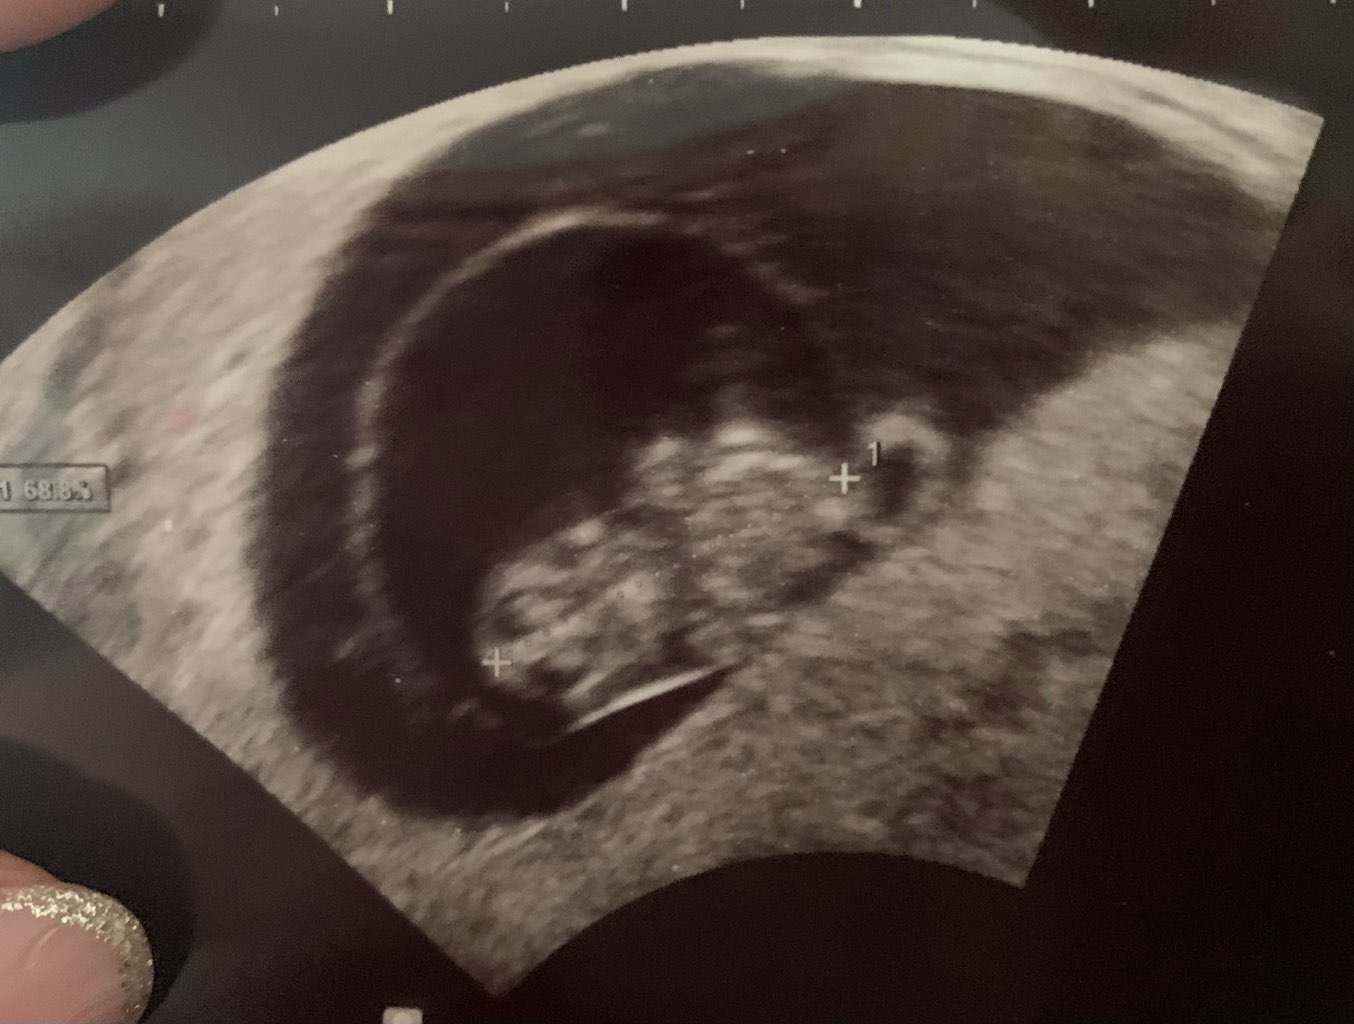

Dziewczyny, melduje że jestem po wizycie. Wszystko gra, serce jak dzwon :). Według usg 8+0, fasolka ma 1,74cm :). Z moją historią będę miała częściej usg, już mam tez skierowanie na prenatalne :). A plamienie to nawet nie krwiak tylko jakaś bulka, z której spada trochę starych skrzepów i mam się nie przejmować, ale nie dźwigać, a w razie w dostałam tabletki do 12tc :).